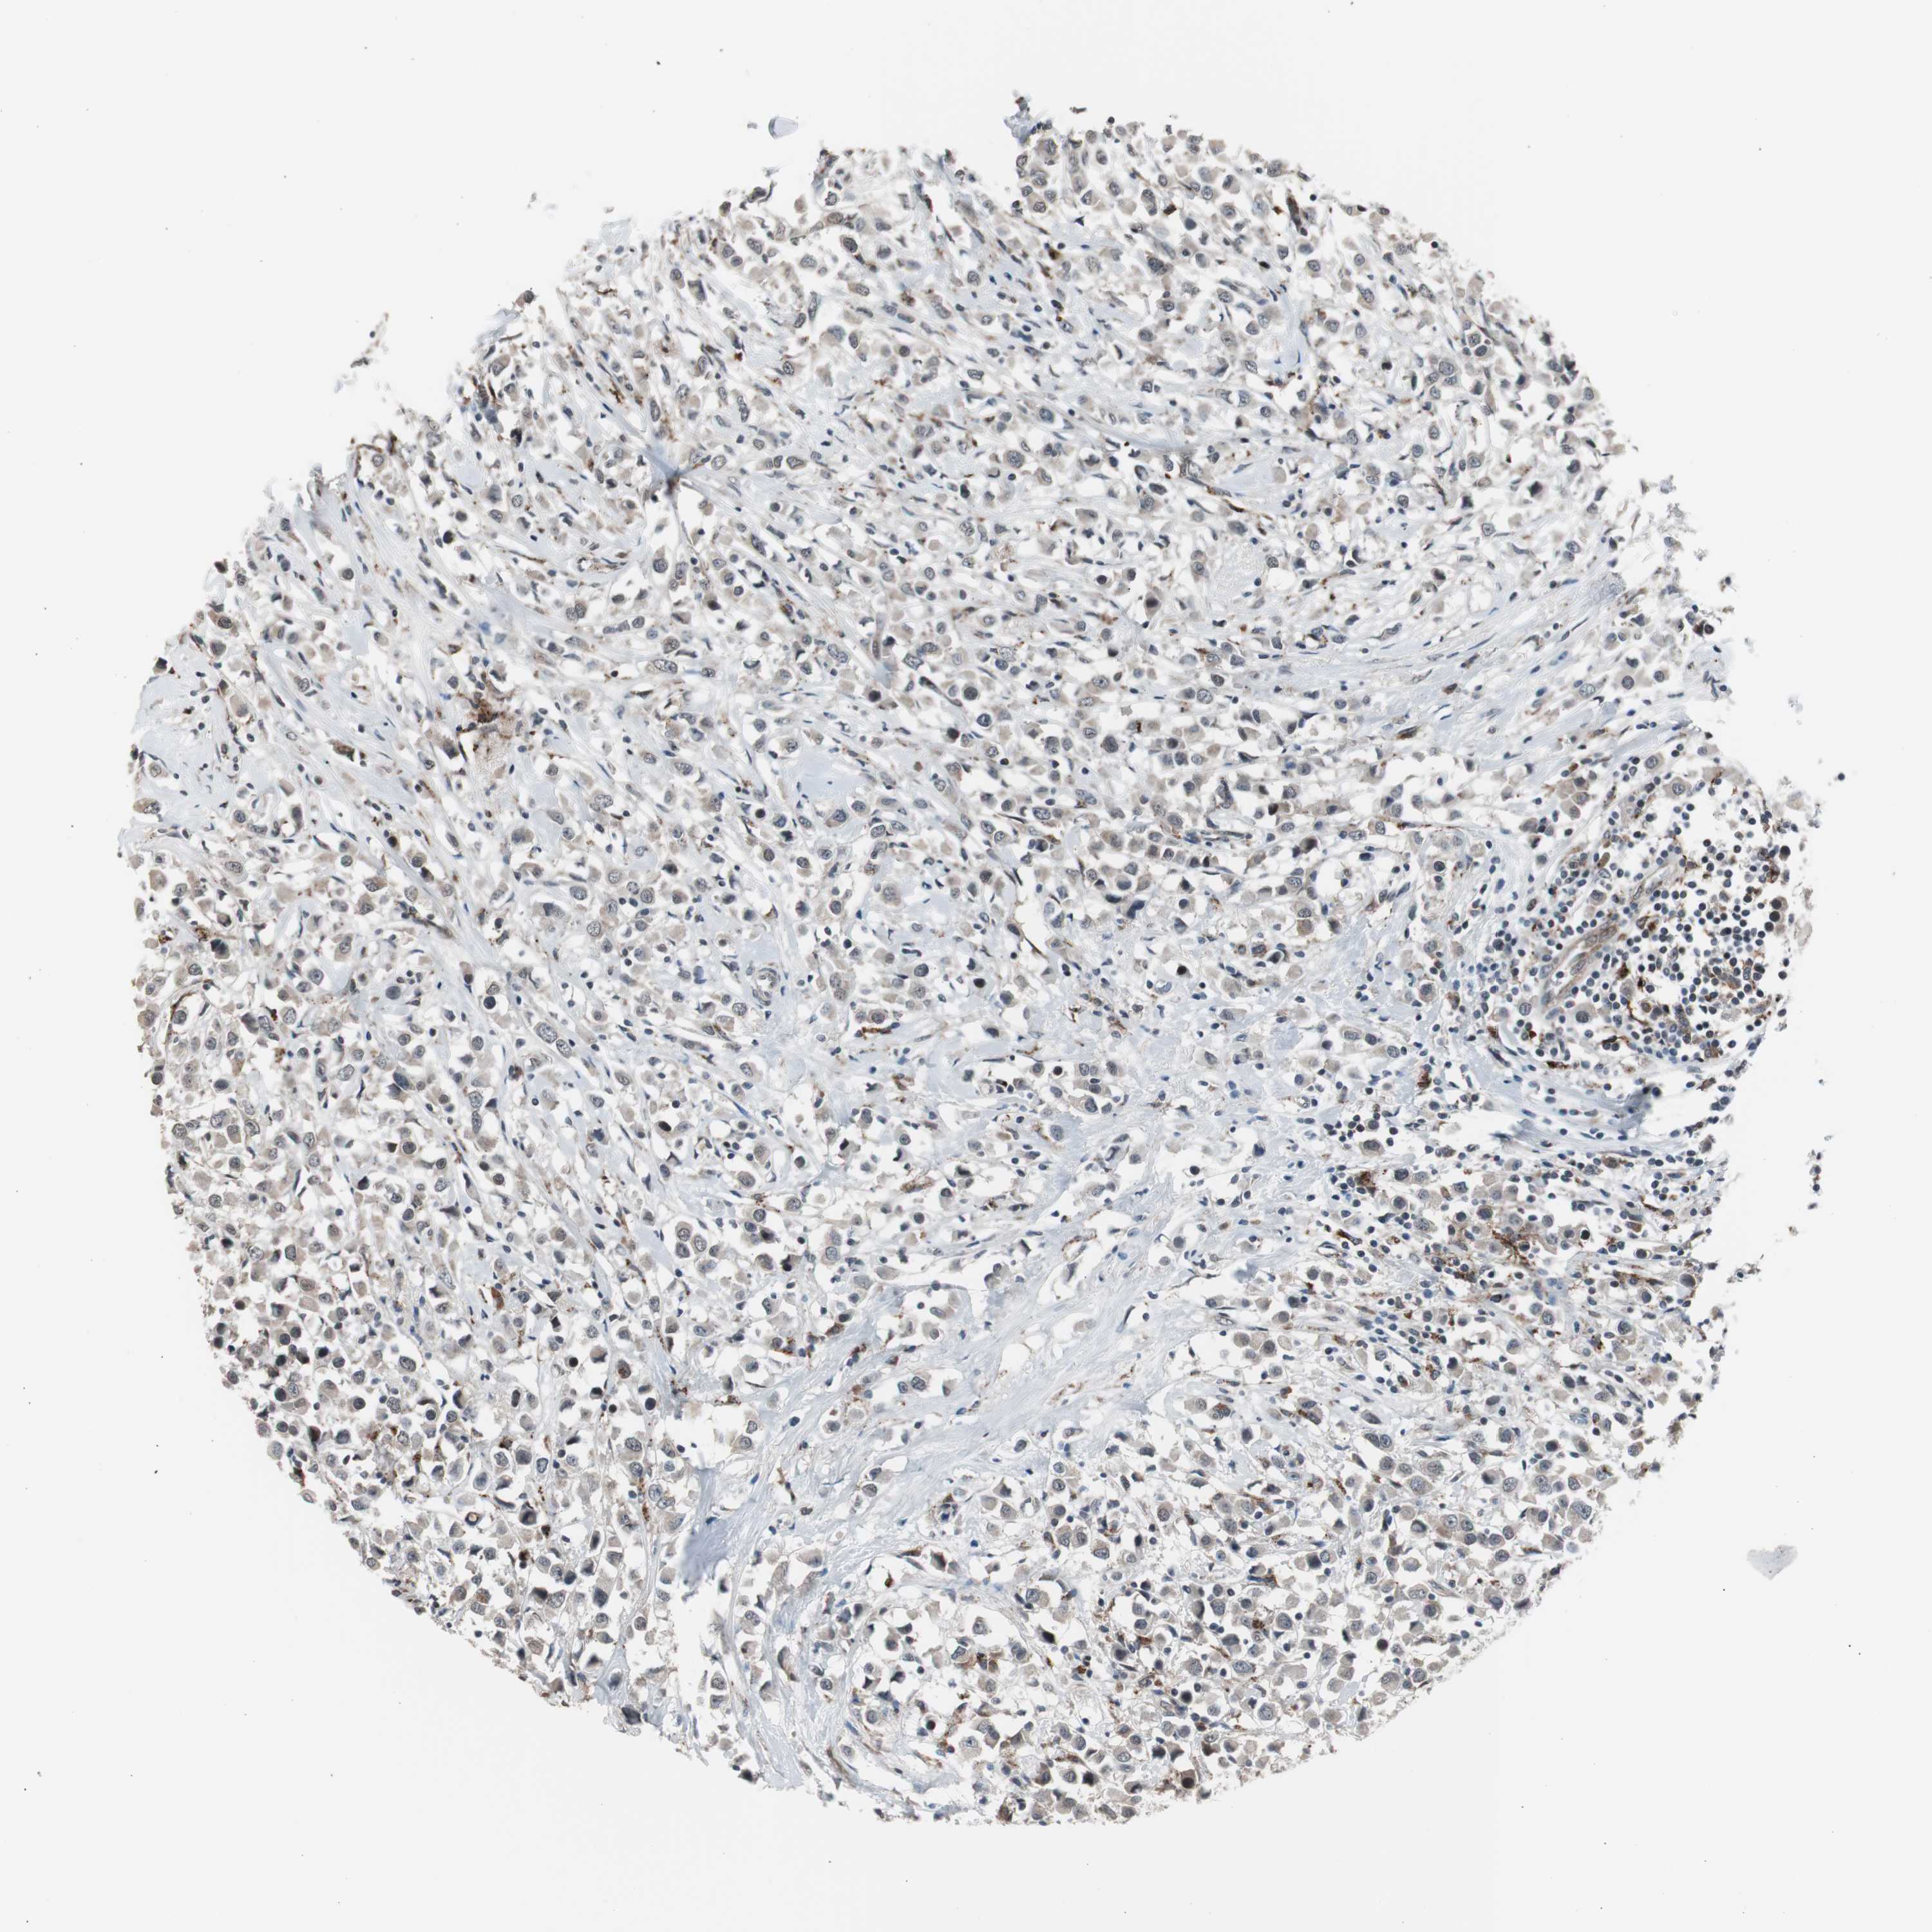

BRCA TCGA BRCA VALIDATION PROTEIN EXPRESSION